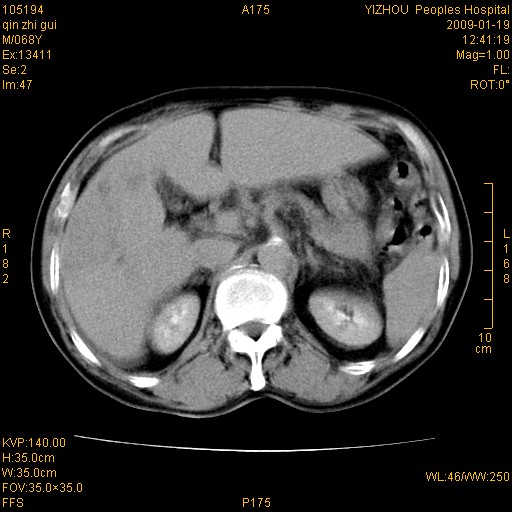

以下是引用随光逐影在2009-1-21 16:11:00的发言:[br]1)考虑肝右叶肝癌并肝静脉及门静脉瘤栓形成。2)肝硬化,少量腹水。3)胆囊炎。4)右侧少量胸腔积液。

病灶外缘凹凸不平,平扫低密度,增强动脉期有强化,门脉早显,静脉期及延期呈延迟强化,结合病史考虑右肝前叶巨块型肝癌可能性大,强化表现不除外胆管细胞癌